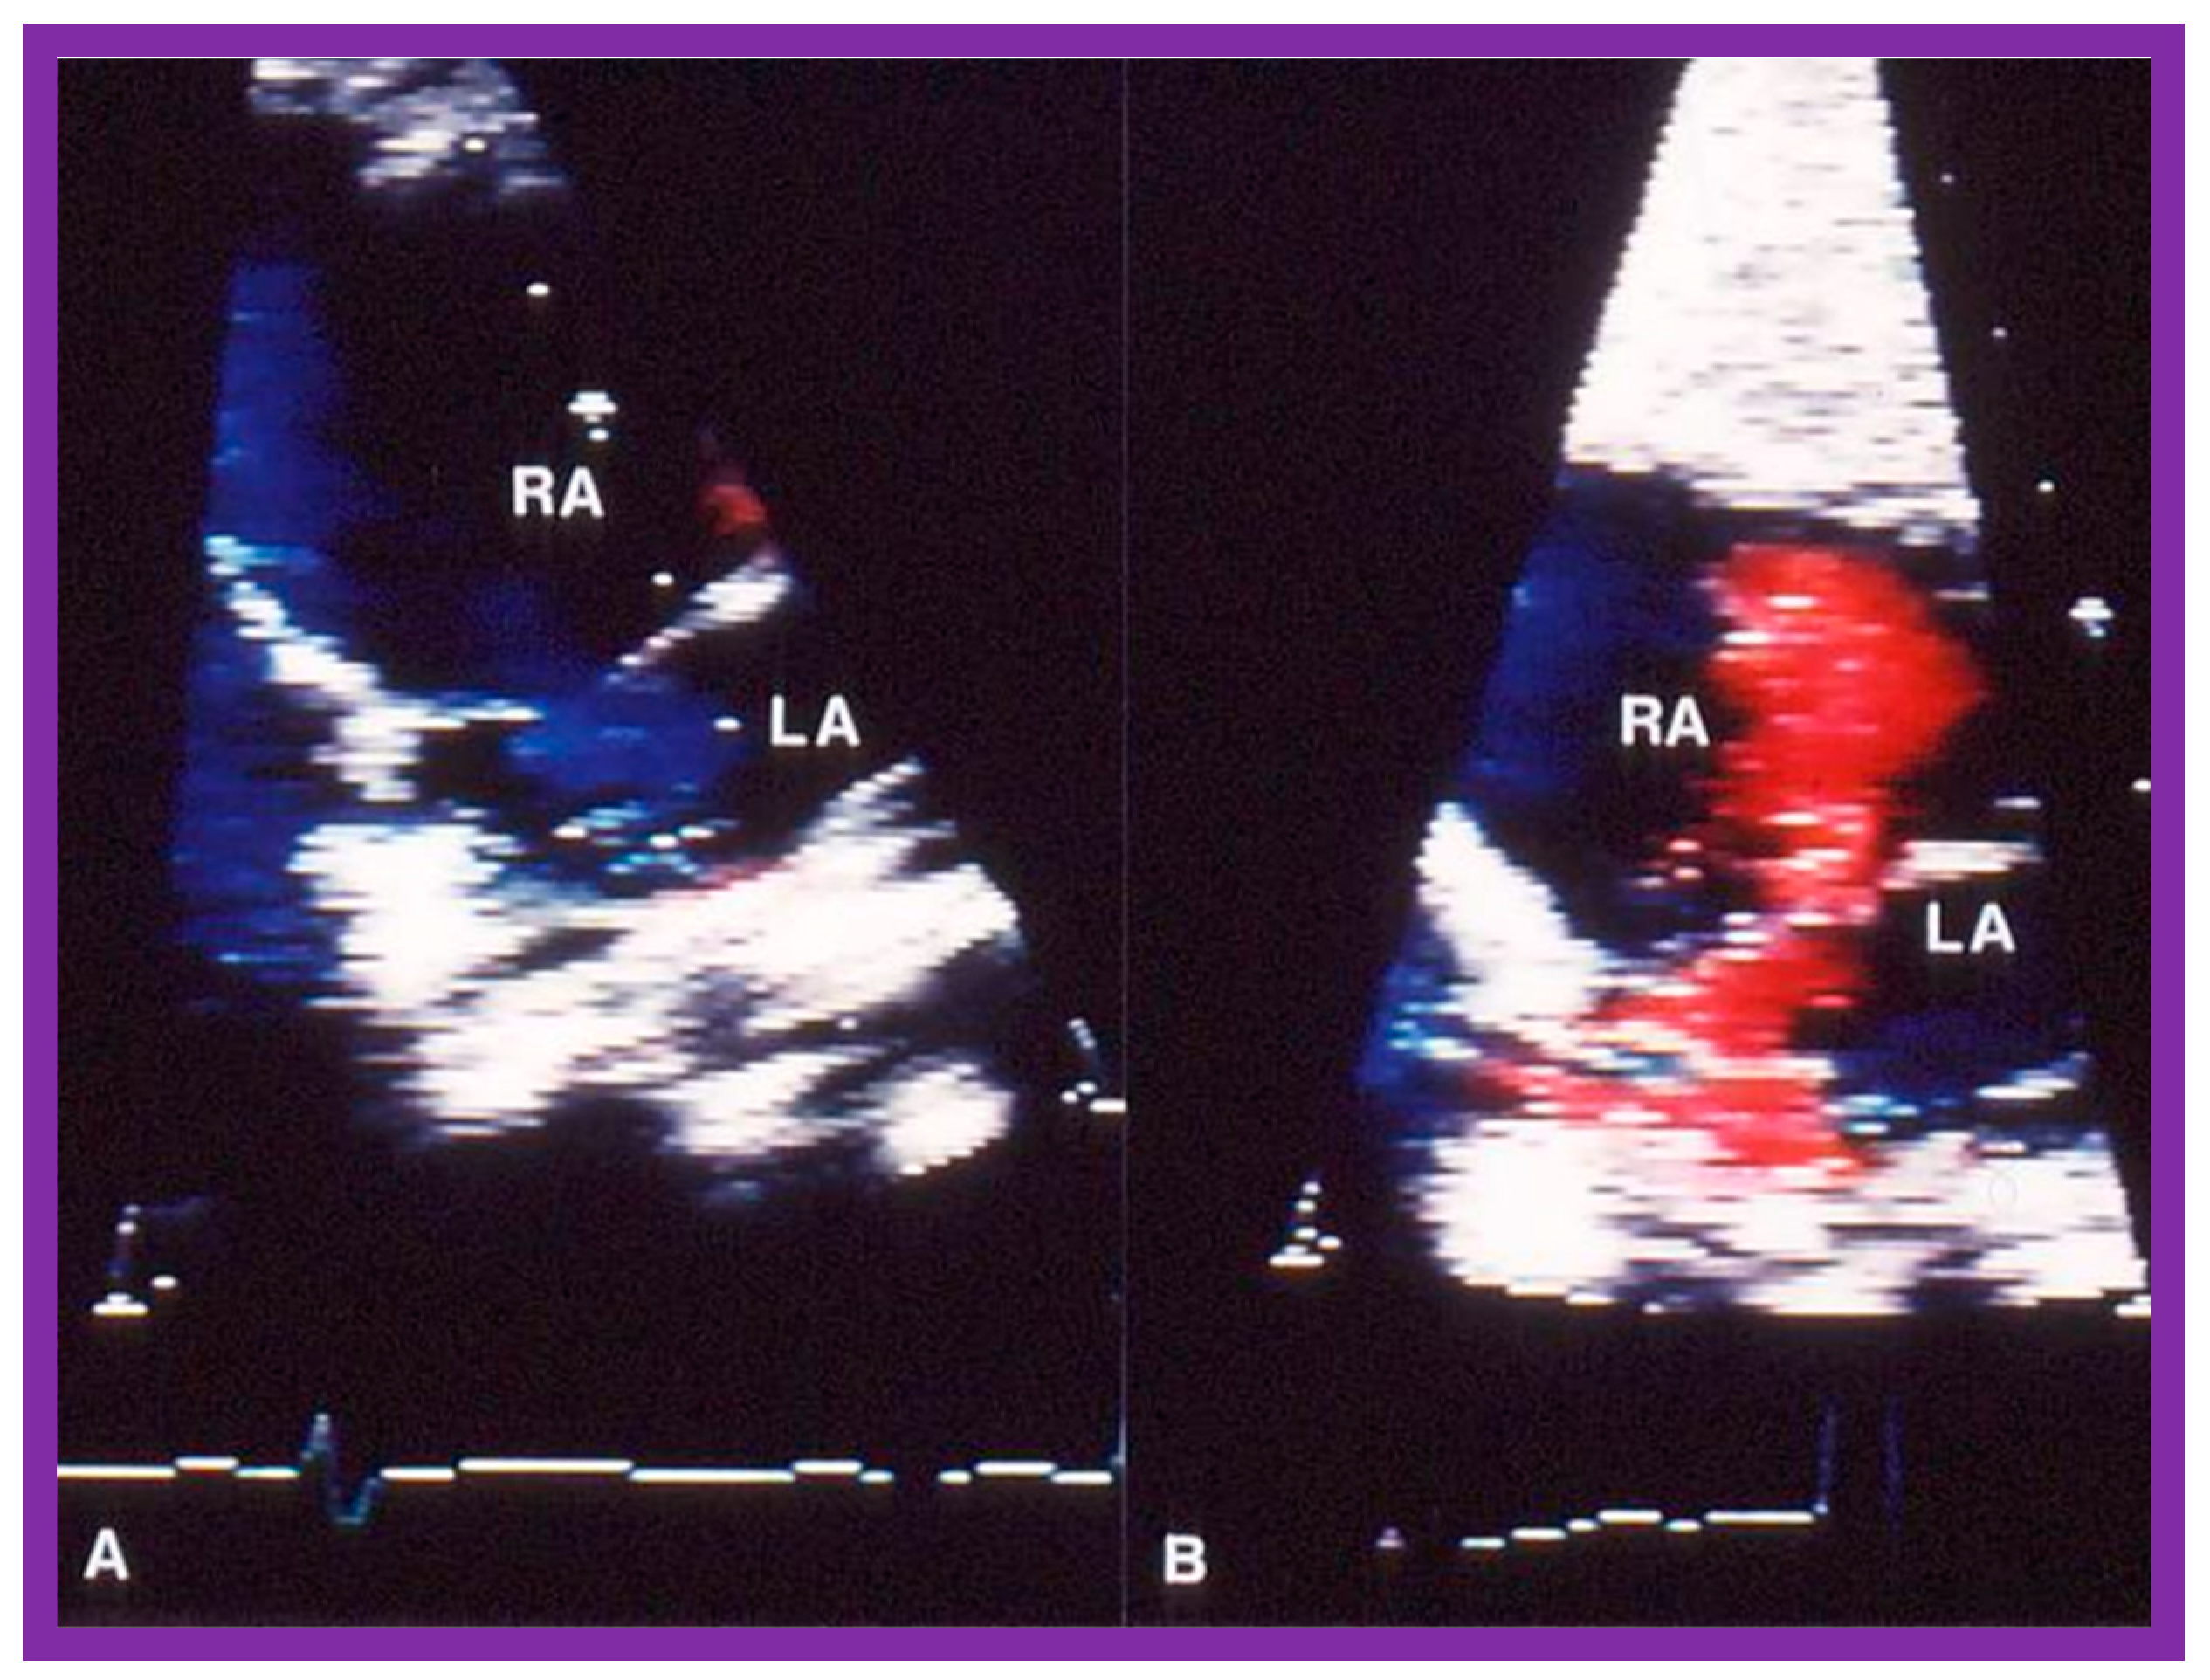

6.2.4. Development of Aortic Insufficiency

6.2.5. Summary of Long-Term Results